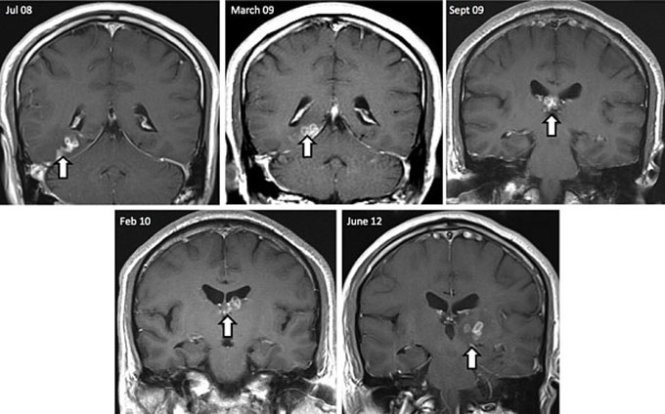

Giun chó làm tổ tưởng nhầm u não

Năm 2013, trường hợp nhiễm giun sán chó nhưng tưởng nhầm u não của nữ công nhân may Lưu T.T (21 tuổi, Thái Bình) cũng khiến dư luận xôn xao.

Theo báo Sức khỏe đời sống, một tháng trước khi nhập viện, bệnh nhân này xuất hiện liên tiếp các cơn đau đầu vùng đỉnh tăng dần, kèm theo có sốt nhẹ nhưng không liệt, co giật.

Với những triệu chứng trên, T. nghĩ mình bị u não và đến khám tại Trung tâm Y học hạt nhân và Ung bướu (Bệnh viện Bạch Mai).

Xét nghiệm công thức máu của bệnh nhân, các bác sĩ phát hiện bạch cầu ái toan tăng cao 20% (bình thường chỉ 0-8%), hình ảnh chụp MRI sọ não không thấy có u hay tổn thương. Tuy nhiên bệnh nhân lại dương tính với giun đũa chó.

Trường hợp này đã được các bác sĩ kịp thời chuyển sang tại Viện sốt rét ký sinh trùng côn trùng trung ương và phát hiện T. bị tổn thương thần kinh trung ương do nhiễm giun đũa chó.